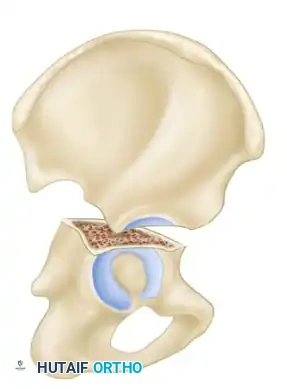

The Letournel and Judet classification system remains the universally accepted framework for categorizing acetabular fractures. It is predicated on the concept of the acetabulum being supported by an inverted "Y" consisting of an anterior column and a posterior column. The system divides fractures into two broad categories: Simple Fracture Types and Associated Fracture Types.

- Transverse Fractures: A single fracture line crosses both the anterior and posterior columns horizontally, dividing the innominate bone into a superior (iliac) segment and an inferior (ischiopubic) segment.

- T-Shaped Fractures: A transverse fracture with an additional vertical fracture line that splits the inferior ischiopubic segment, exiting through the obturator ring.

- Both-Column Fractures: The most complex pattern. All articular segments are detached from the intact posterior ilium (which remains attached to the sacrum).

Secondary Congruence in Both-Column Fractures

A unique phenomenon observed exclusively in both-column fractures is "secondary congruence." Because all articular fragments are detached from the axial skeleton, they can occasionally settle concentrically around the medially displaced femoral head.

If the articular cartilage space is preserved and the femoral head remains concentrically enveloped by the fragments (despite medialization of the entire joint complex), nonoperative treatment via skeletal traction can yield surprisingly excellent long-term functional results.